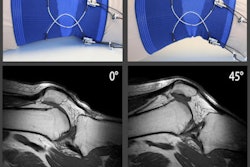

The 26 patients underwent a standard clinical knee exam, which included an evaluation of the ACL and a further inspection to exclude any concomitant injuries. After the assessment, the patients were referred for a 1.5-tesla MRI scan (Maestro Sonata, Siemens Healthineers) of the injured knee. The results were interpreted in a blinded manner by three readers: a musculoskeletal radiologist with 15 years of experience interpreting knee MRI scans, a musculoskeletal radiologist with eight years of experience, and an orthopedic surgeon with 10 years of experience.

A preoperative MRI scan can be valuable in assessing damage to the anterolateral structures of the knee caused by an ACL injury. Image courtesy of Dr. Edoardo Monaco.After the MRI scan, all of the patients underwent ACL reconstruction within 10 days of their injury as part of the standard care for acute ACL ruptures at Sant'Andrea Hospital in Rome. At the time of the procedure, macroscopic injuries were identified, which allowed the researchers to determine correlations between MRI and surgical exploration findings.